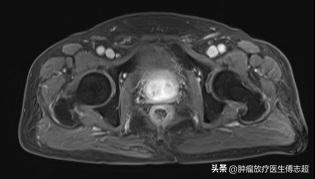

2016年3月复查PSA0.27ng/ml ,2016年12月复查PSA 0.64ng/ml ,2017年2月17日复查(图1)PSA:1.62ng/ml,睾酮17.77ng/dl,2017年5月24日复查 PSA 2.0ng/ml,睾酮23ng/dl,2017年7月6日因冠脉综合症伴心衰停止内分泌治疗。

图1 2017-2-8放射治疗1年半后复查盆腔MRI